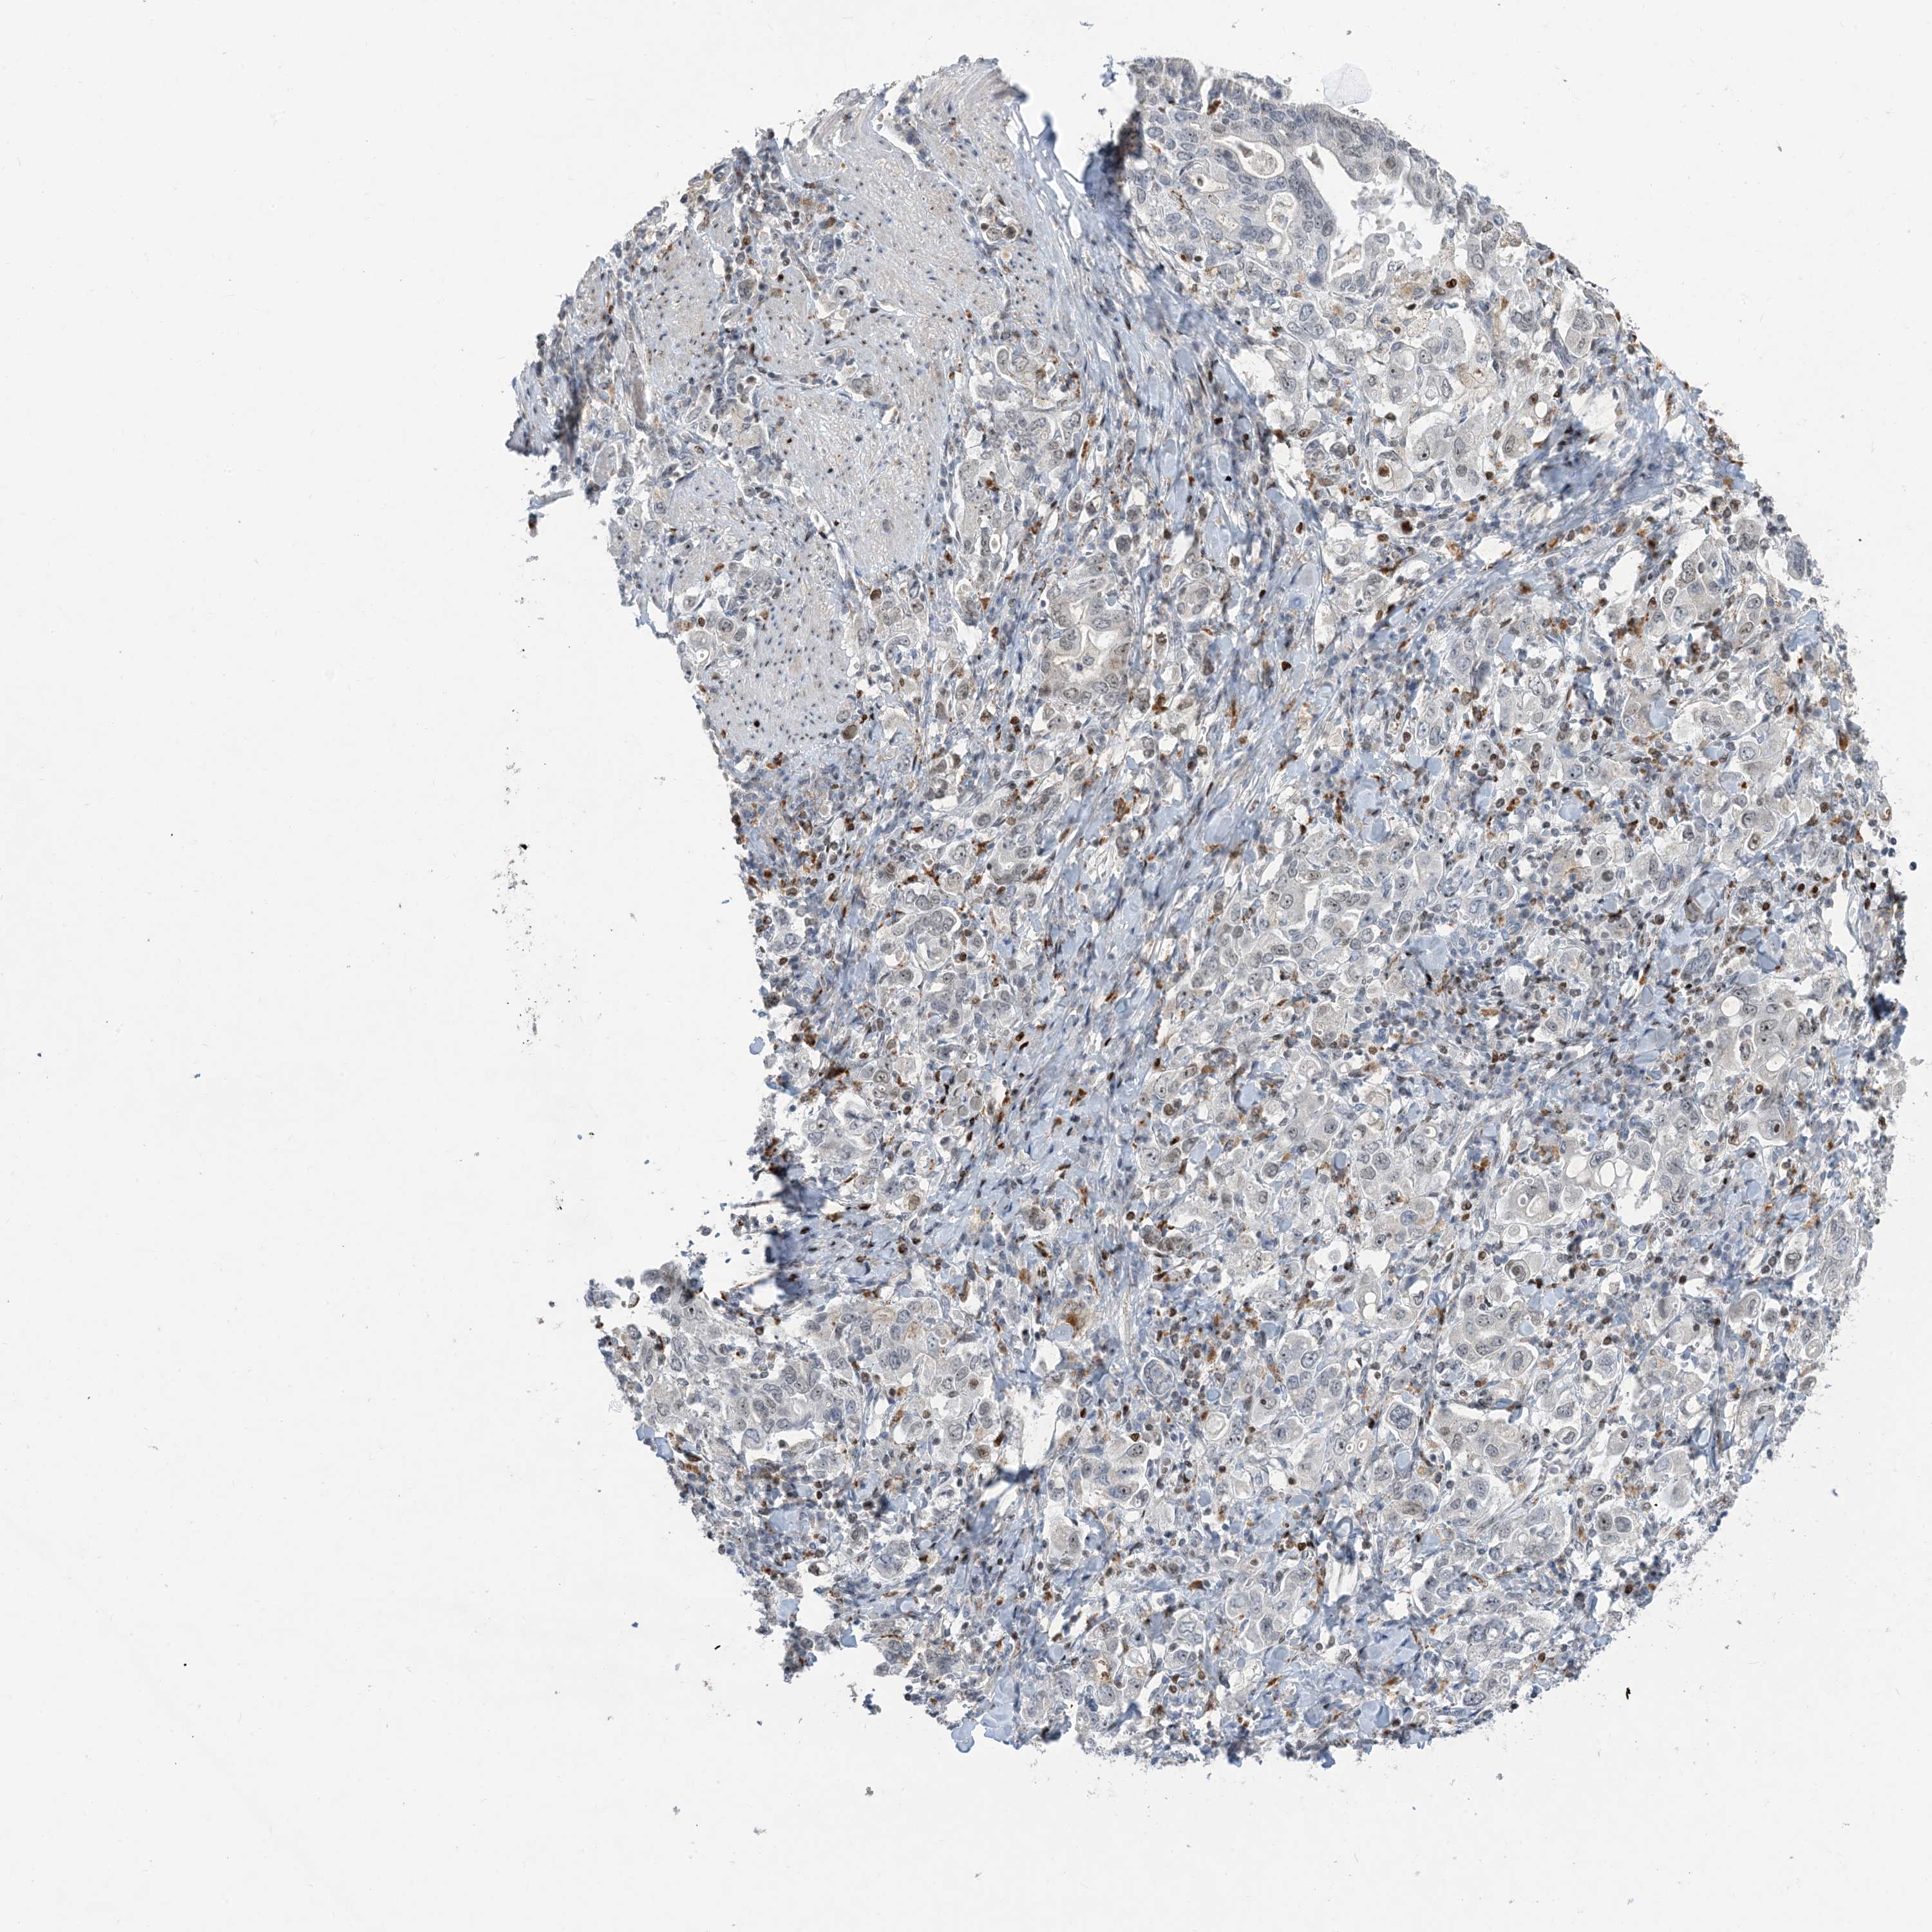

STOMACH CANCER - Protein expressioni

A mouse-over function shows sample information and annotation data. Click on an image to view it in a full screen mode. Samples can be filtered based on level of antibody staining by selecting one or several of the following categories: high, medium, low and not detected. The assay and annotation is described here.

Note that samples used for immunohistochemistry by the Human Protein Atlas do not correspond to samples in the TCGA dataset.

Antibody stainingi

Antibody staining in the annotated cell types in the current human tissue is reported as not detected, low, medium, or high, based on conventional immunohistochemistry profiling in selected tissues. This score is based on the combination of the staining intensity and fraction of stained cells.

Each image is clickable and will lead to virtual microscopy that enables deeper exploration of all samples and also displays staining intensity scores, fraction scores and subcellular localization as well as patient and tissue information for each sample.

Antibody HPA034959

Staining

High

Medium

Low

Not detected

Intensity

Strong

Moderate

Weak

Negative

Quantity

>75%

75%-25%

<25%

None

Location

Nuclear

Cytoplasmic/membranous

Cytoplasmic/membranous,nuclear

Adenocarcinoma, NOS